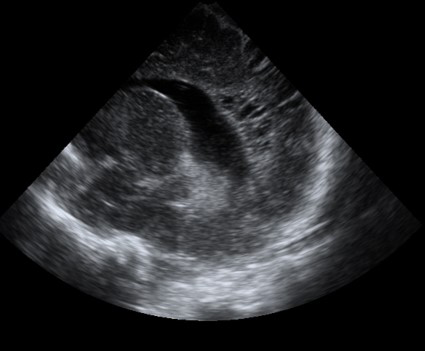

Neonatology PVHI Thalamus 4 Image